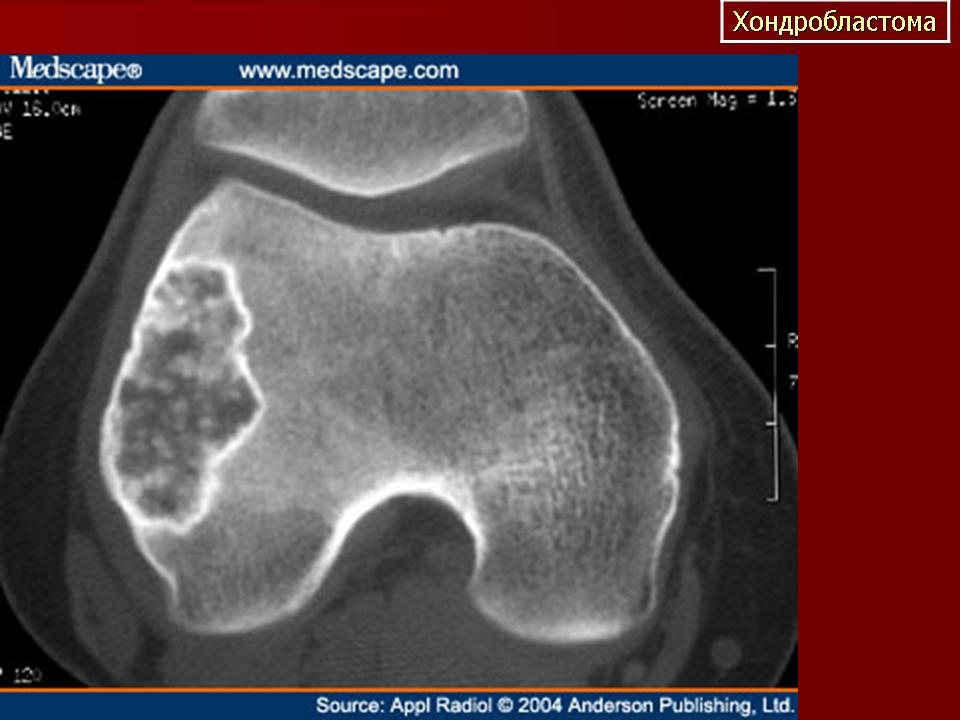

Хондробластома. Встречается в 1,0-1,8% первичных опухолей костей, преимущественно у лиц мужского пола в возрасте от 10 до 25 лет. Чаще всего хондробластомы возникают в эпифизарных отделах длинных трубчатых костей, реже - в лопатке, ребрах, надколеннике, костях кисти и стоп. Клинически характеризуются несильными болями в суставе, наличием болезненной припухлости и иногда ограничением движений в суставе. Рентгенологически в пораженной кости выявляется очаг просветления округлой или овальной формы; рисунок очага неоднородный, крапчатый. Опухоль ограничена зоной склероза. Частым признаком является периостальная реакция. Лечение хирургическое: широкая резекция кости с замещением дефекта трансплантатом.

Хондробластома. В 1931 году Codman подробно описал это новообразование костей под названием «эпифизарная хондроматозная гигантоклеточная опухоль». В литературе можно встретить описание ее под названием опухоли Кодмена. В 1942 году Jaffe и Lichtenstein выделили эту опухоль в самостоятельную форму под названием «хондробластома», состоящую в основном из хондробластов.

Хондробластома — это редкая опухоль. Судя по данным литературы, она составляет 1—1,8% среди первичных опухолей костей. Болеют лица обоего поля, но чаще— мужского. Хондробластома встречается в любом возрасте, но преимущественно — в детском и юношеском (10—25 лет). Излюбленная локализация — длинные трубчатые кости. Реже хондробластома расположена в лопатке, ребре, пяточной кости, костях кисти и стопы. В длинных трубчатых костях ходробластома поражает эпифиз и метафиз (проксимальный и дистальный отделы бедренной кости, проксимальный — большеберцовой и плечевой кости, проксимальный отдел лучевой кости). Хондробластома распространяется в сторону сустава и в ряде случаев отмечается реактивный выпот в суставе. Патологические переломы наблюдаются редко.

В клинической картине превалирует боль в месте поражения и в соседнем суставе. Отмечается небольшая припухлость, иногда ограничение движений в суставе и атрофия мышц конечности.

Рентгенологическая картина имеет ряд особенностей. Определяется очаг деструкции округлой или овальной формы. Он не однороден. Вследствие наличия в опухоли участков обызвествления, на рентгенограмме видны крапчатые тени. При субкортикальном расположении очага возможна небольшая периостальная реакция. Кортикальный слой может быть истончен, иногда целостность его нарушается и опухоль выходит за пределы кости, что не является, как и при остеобластокластоме, признаком ее малигнизации.